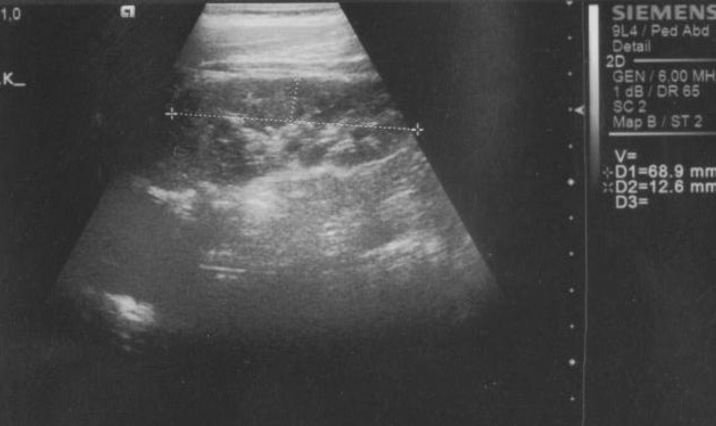

A 1-year old male patient presented because stones were found on US which was performed following urinary tract infection at the age of six months. In his history, it was learned that the mother and two daughters of the mother from the previous marriage had renal stones and the uncle was lost because of chronic renal failure 14 years ago. System findings were found to be normal on physical examination. Multiple calcifications with the larges one being 2 cm were found in both kidneys on repeated urinary tract US (see figure).